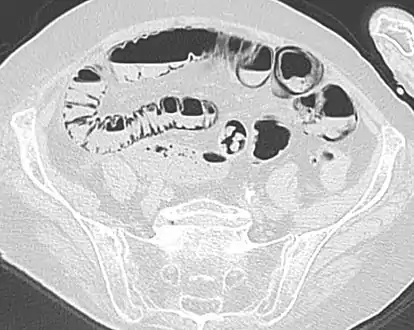

Coronal reformatted MDCT image showing extensive pneumatosis intestinalis in the left upper quadrant small bowel. The pneumatosis is more cystic and nodular in the small bowel in the midline and the right of midline. This patient had a relatively benign presentation without bowel ischemia and was treated conservatively.